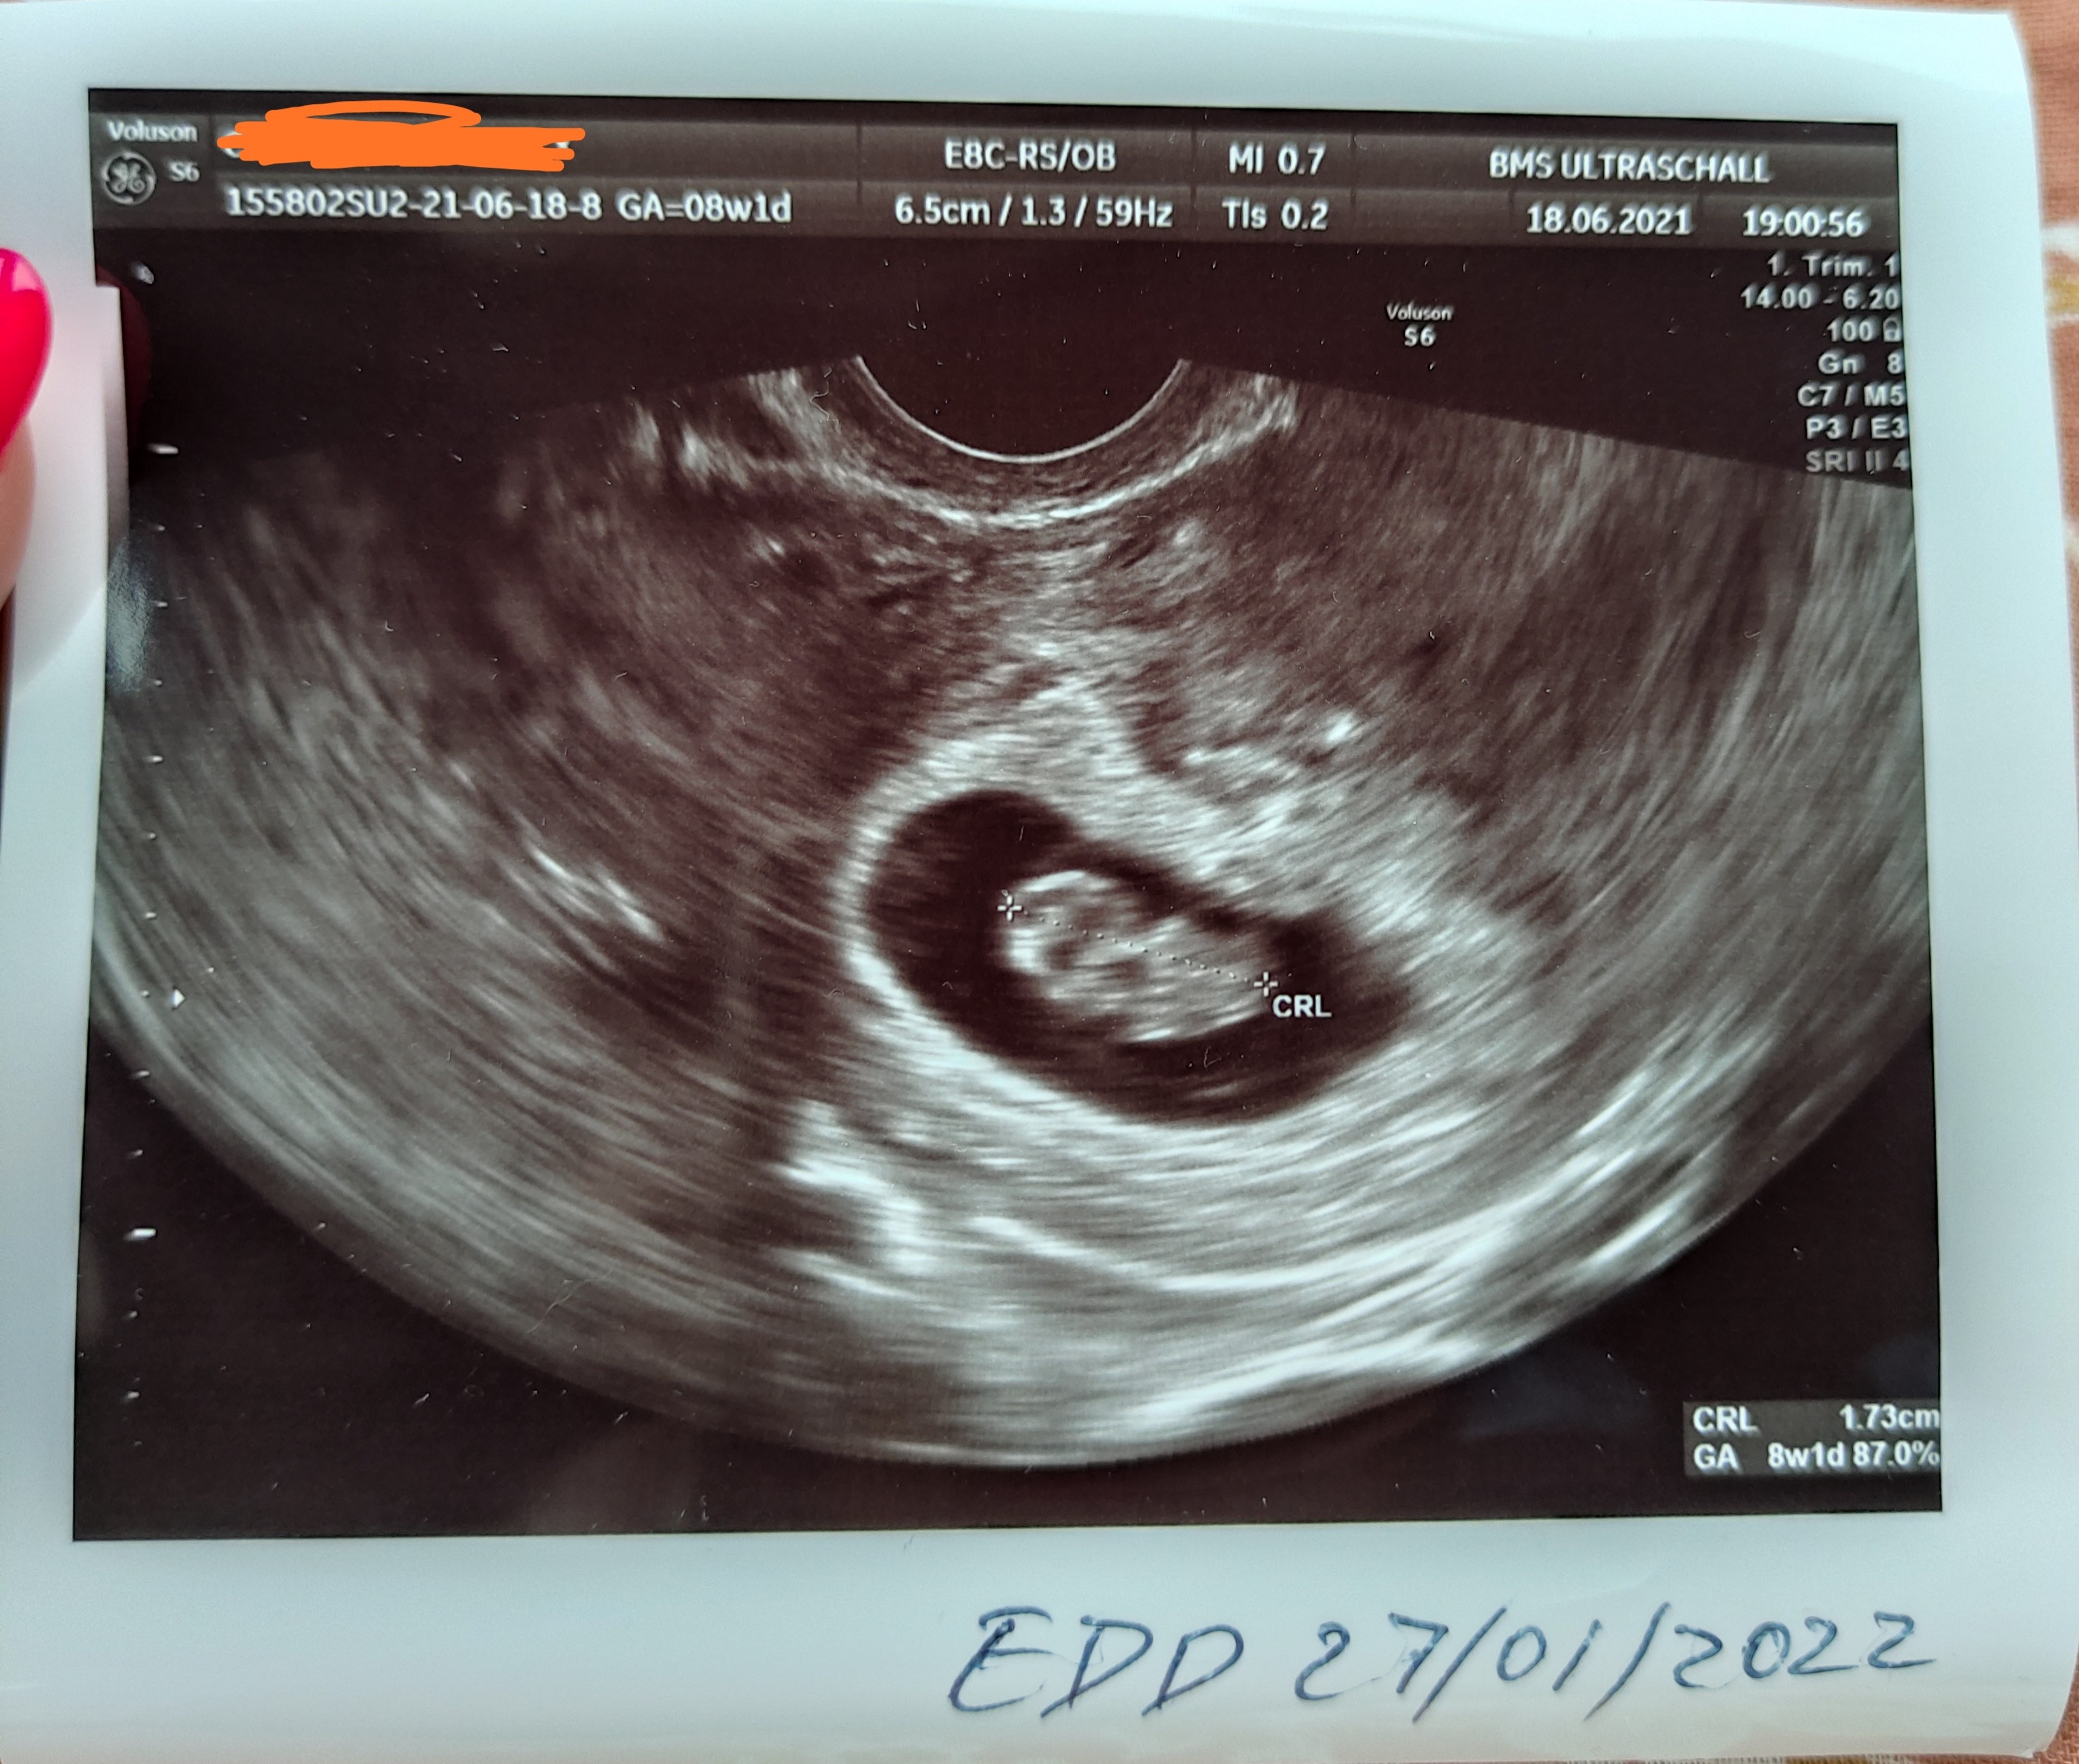

1 wizyta 4.06 5t5d z om potwierdzona ciaza (widoczny pęcherzyk ciążowy, kropeczka cialka żółtego), 11.06 6t5d z om pierwsze usg ze zdjęciem - ciałko żółte 3,78mm, pęcherzyk ciążowy 9,87mm, zawiazki zarodka i brak serca, trzecia wizyta dzisiaj 7t5d z om - bez pomiarów bo to u doktor prowadzącej - jest spory pierścień i zarodek ale brak serca. Kolejne USG za tydzien z pomiarami. Zaczynam tracić nadzieje, cykle co prawda 30-31 dni ale tak liczyłam na to, ze dzisiaj już coś będzie pulsowało na usg